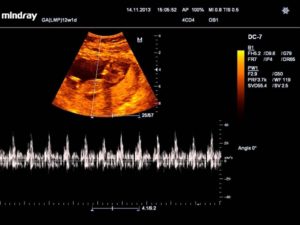

Оптимальным сроком обследования сердца ребенка в утробе ультразвуковым датчиком считается двенадцатая неделя беременности.

В это время при анализе сердца зародыша видно, как работает сердечно-сосудистая система, и не составляет сложности определить результаты ее функционирования. Тем не менее, проводится осмотр и на более раннем или позднем сроках.

Внеплановая диагностика назначается в случае подозрения на серьезную патологию, чтобы начать лечение как можно раньше или прервать беременность при необходимости.

На кушетке пациентке придется пробыть около получаса, именно столько врач-диагност будет проводить исследование.

Беременная ложится на спину и освобождает живот от одежды. Врач использует проводниковый гель, чтобы получить более достоверный результат.

Если срок беременности – как минимум двадцать недель, процедура проводится трансабдоминально, чтобы избежать стимуляции тонуса матки.

Уже через несколько минут после проведения обследования врач выдает на руки женщине расшифровку результатов.